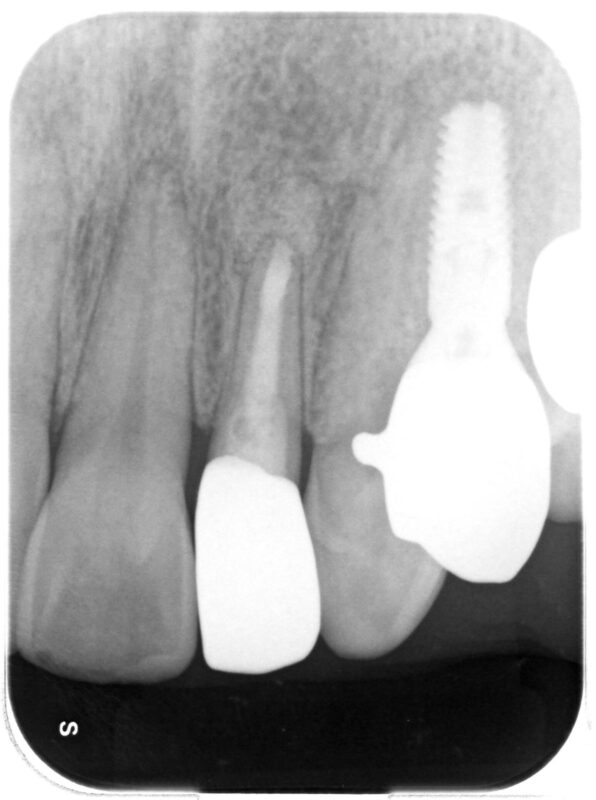

術後1年

綺麗に治っています。

右側、歯根破折を起こしていた歯牙にはインプラント治療を行っています。